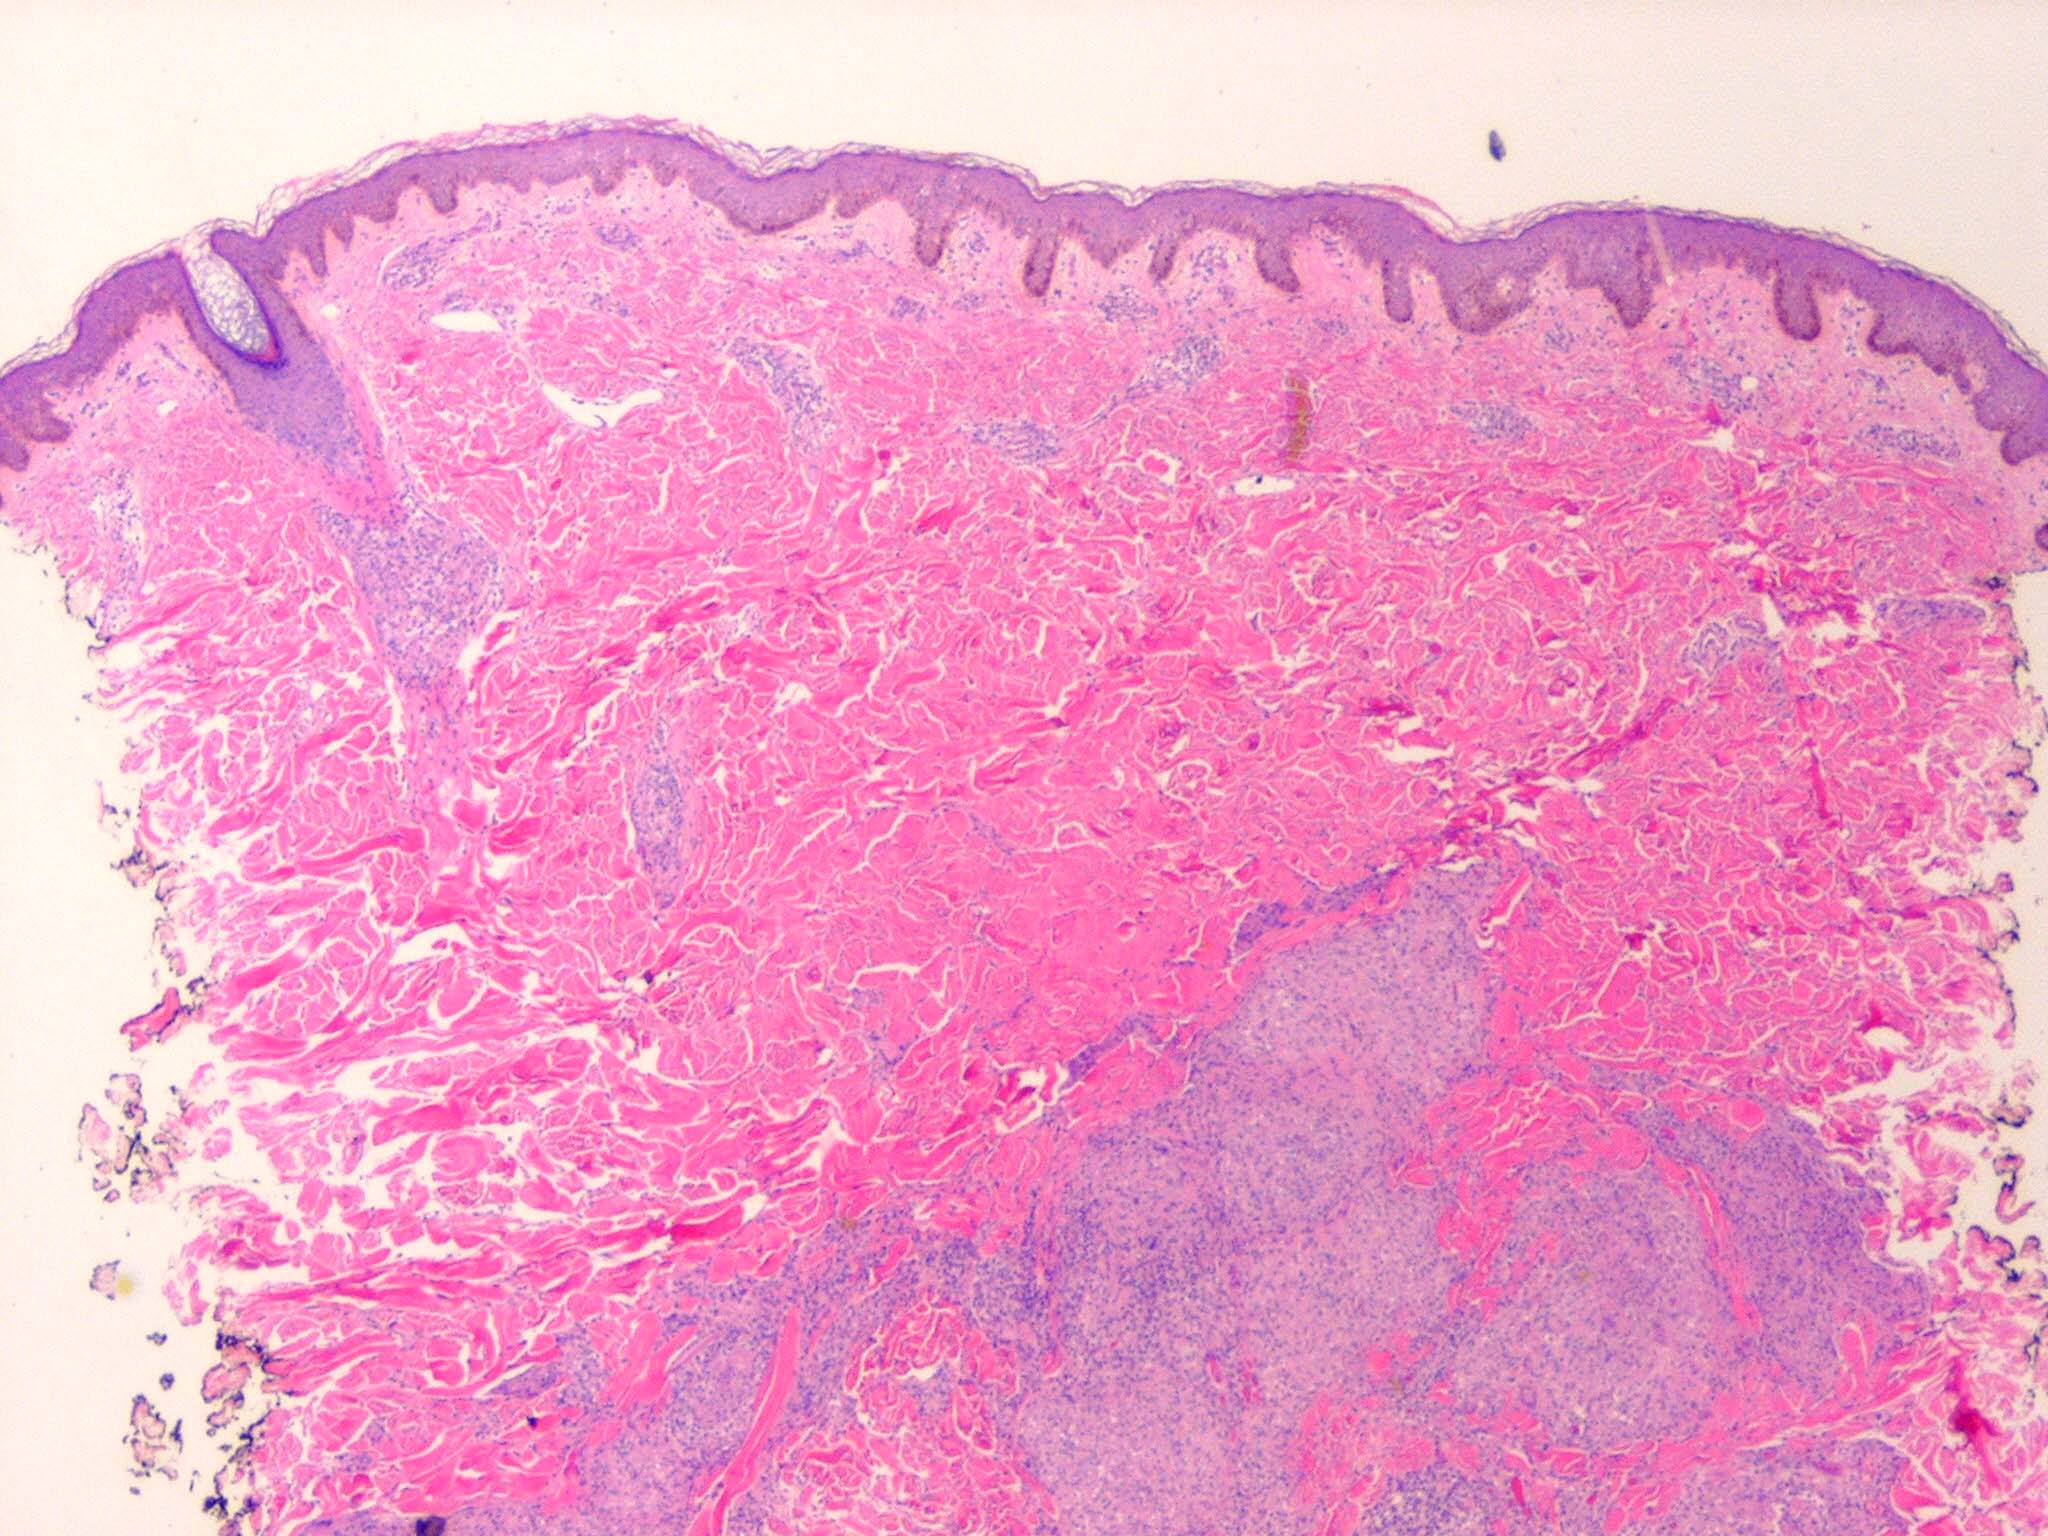

Like lesions in other organs, the cutaneous lesions of chronic, persistent sarcoidosis are characterized by the presence of circumscribed collections of epithelioid histiocytes-so-called epithelioid cell tubercles-which show little or no necrosis .

The papules, plaques, and lupus pernio-type lesions show variously sized aggregates of epithelioid cells scattered irregularly through the dermis with occasional extension into the subcutis (. In the erythrodermic form, the infiltrate shows small granulomas in the upper dermis intermingled with numerous lymphocytes

and, rarely, also giant cells . Typical sarcoidal granulomas are found in the ichthyosiform lesions , in ulcerated areas , and in atrophic lesions . Verrucous sarcoid exhibits prominent associated acanthosis and hyperkeratosis . Biopsies of

hypopigmented sarcoid may reveal granulomas, which may have a perineural component or fail to reveal granulomas . In subcutaneous nodules, larger epithelioid cell tubercles lie in the subcutaneous fat .